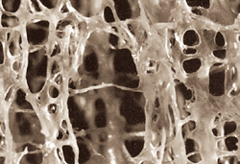

°ñ´Ù°øÁõÀº ´ëÇ¥ÀûÀÎ ´ë»ç¼º °ñÁúȯÀÇ ÀÏÁ¾À¸·Î »ÀÀÇ °ñ·®ÀÌ °¨¼ÒµÇ°í, ¹Ì¼¼ÇÑ »À »çÀÌÀÇ ¿¬°áÀÌ ²÷¾îÁ® »À ¼Ó¿¡ ¸¹Àº ±¸¸ÛÀÌ »ý°Ü¼ ÀÛÀº Ãæ°Ý¿¡µµ ½±°Ô ºÎ·¯ Áö´Â ÁúȯÀÔ´Ï´Ù. ÁÖ·Î °ñÀýÀÌ ¹ß»ýµÇ´Â ºÎÀ§´Â ´ëÅðºÎ, ôÃߺÎ, ¿ä°ñºÎ(¼Õ¸ñ°ñÀý) ÀÔ´Ï´Ù.

<°ñ´Ù°øÁõ ȯÀÚÀÇ »À>